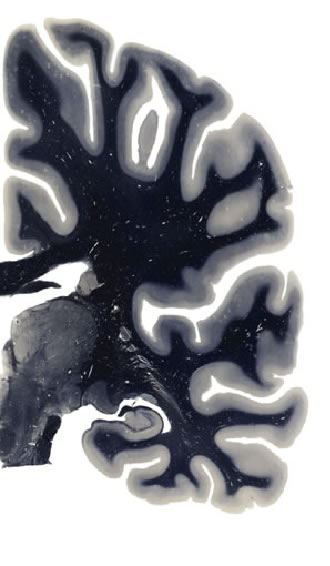

Hi-Resolution Sections · Cells (Nissl Staining) · Virtual Microscopy

Frontal sections (Nissl) from the Atlas Brain:

Slice ID:

r3-0349

Plate NR:

ca 43

Position:

28,0 mm